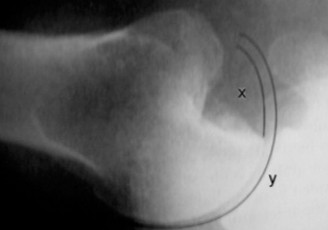

It should be noted that reverse total shoulder arthroplasty is also the procedure of choice in patients with cuff-tear arthropathy (aka rotator cuff arthropathy). Characteristics of cuff-tear arthropathy include superior migration of the humerus due to a massive rotator cuff tear, glenohumeral joint destruction, subchondral osteoporosis, and humeral head collapse (see Fig. 2–17). A reverse total shoulder

Figure 2–17_X-rays of a patient showing evidence of cuff tear arthropathy. The humerus is migrated superiorly, the glenohumeral joint is destroyed, there is subchondral osteoporosis, and the humeral head is collapsed. (From Ecklund KJ, Lee TQ, Tibone J, Gupta R. Rotator cuff tear arthropathy. _J Am Acad Orthop Surg. 2007;15(6):340–349.)